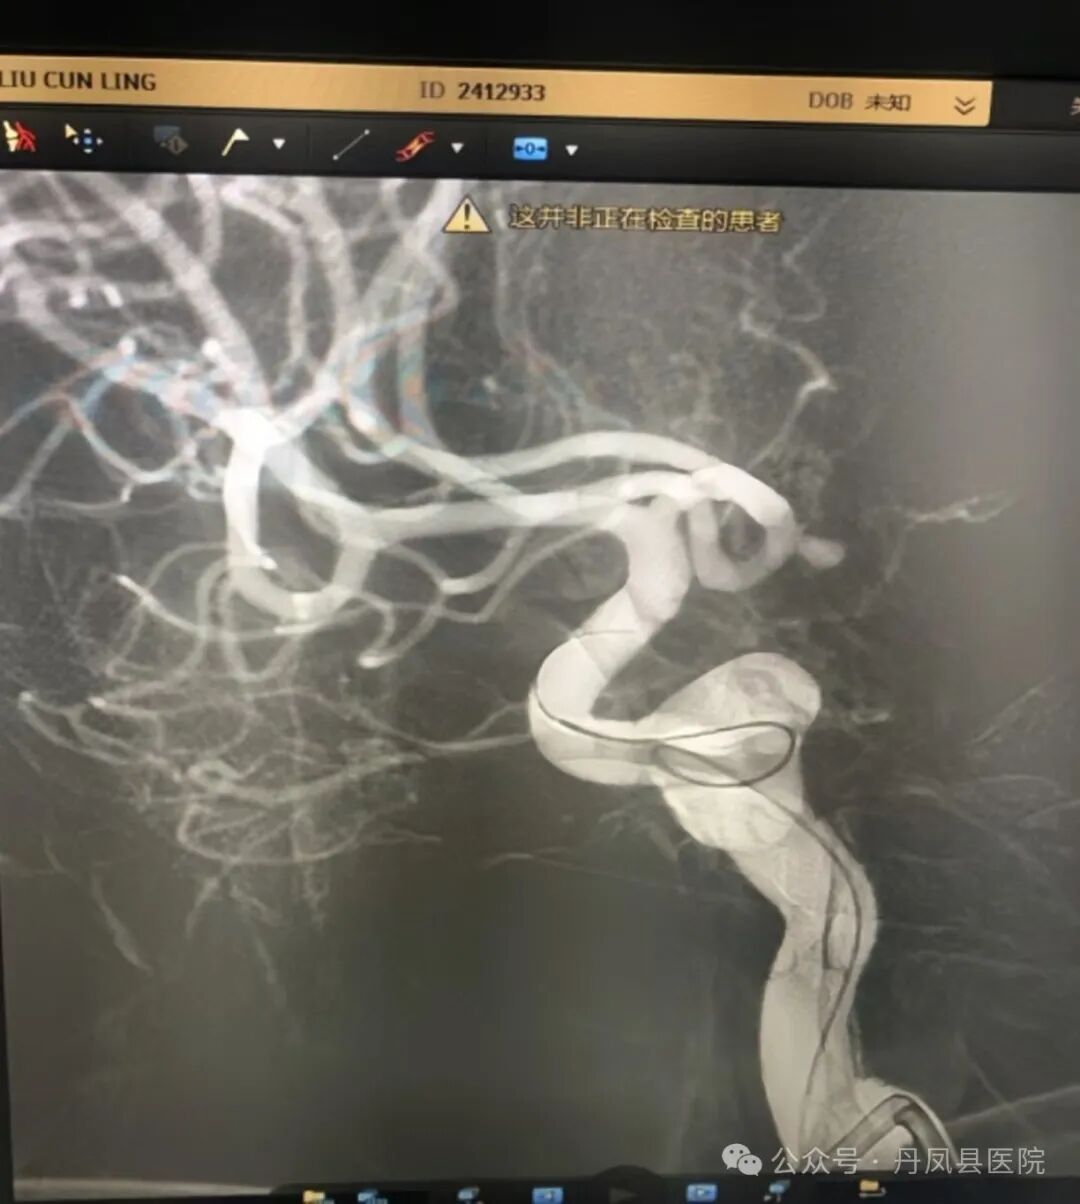

图为造影发现动脉瘤8月28日,在唐都医院神经外科姜海洋教授的现场指导下,神经外科王龙珍主任、刘建锋主治医师及张永昌、赵斌轲医师联合麻醉科、介入室进行了多学科讨论,评估手术安全,最终,成功为患者实施了颅内前交通动脉瘤介入栓塞术,手术顺利,动脉瘤体被致密填塞,术后患者麻醉清醒,无神经功能受损表现。![]()

图为介入手术置入导管

图为动脉瘤介入栓塞后![]()